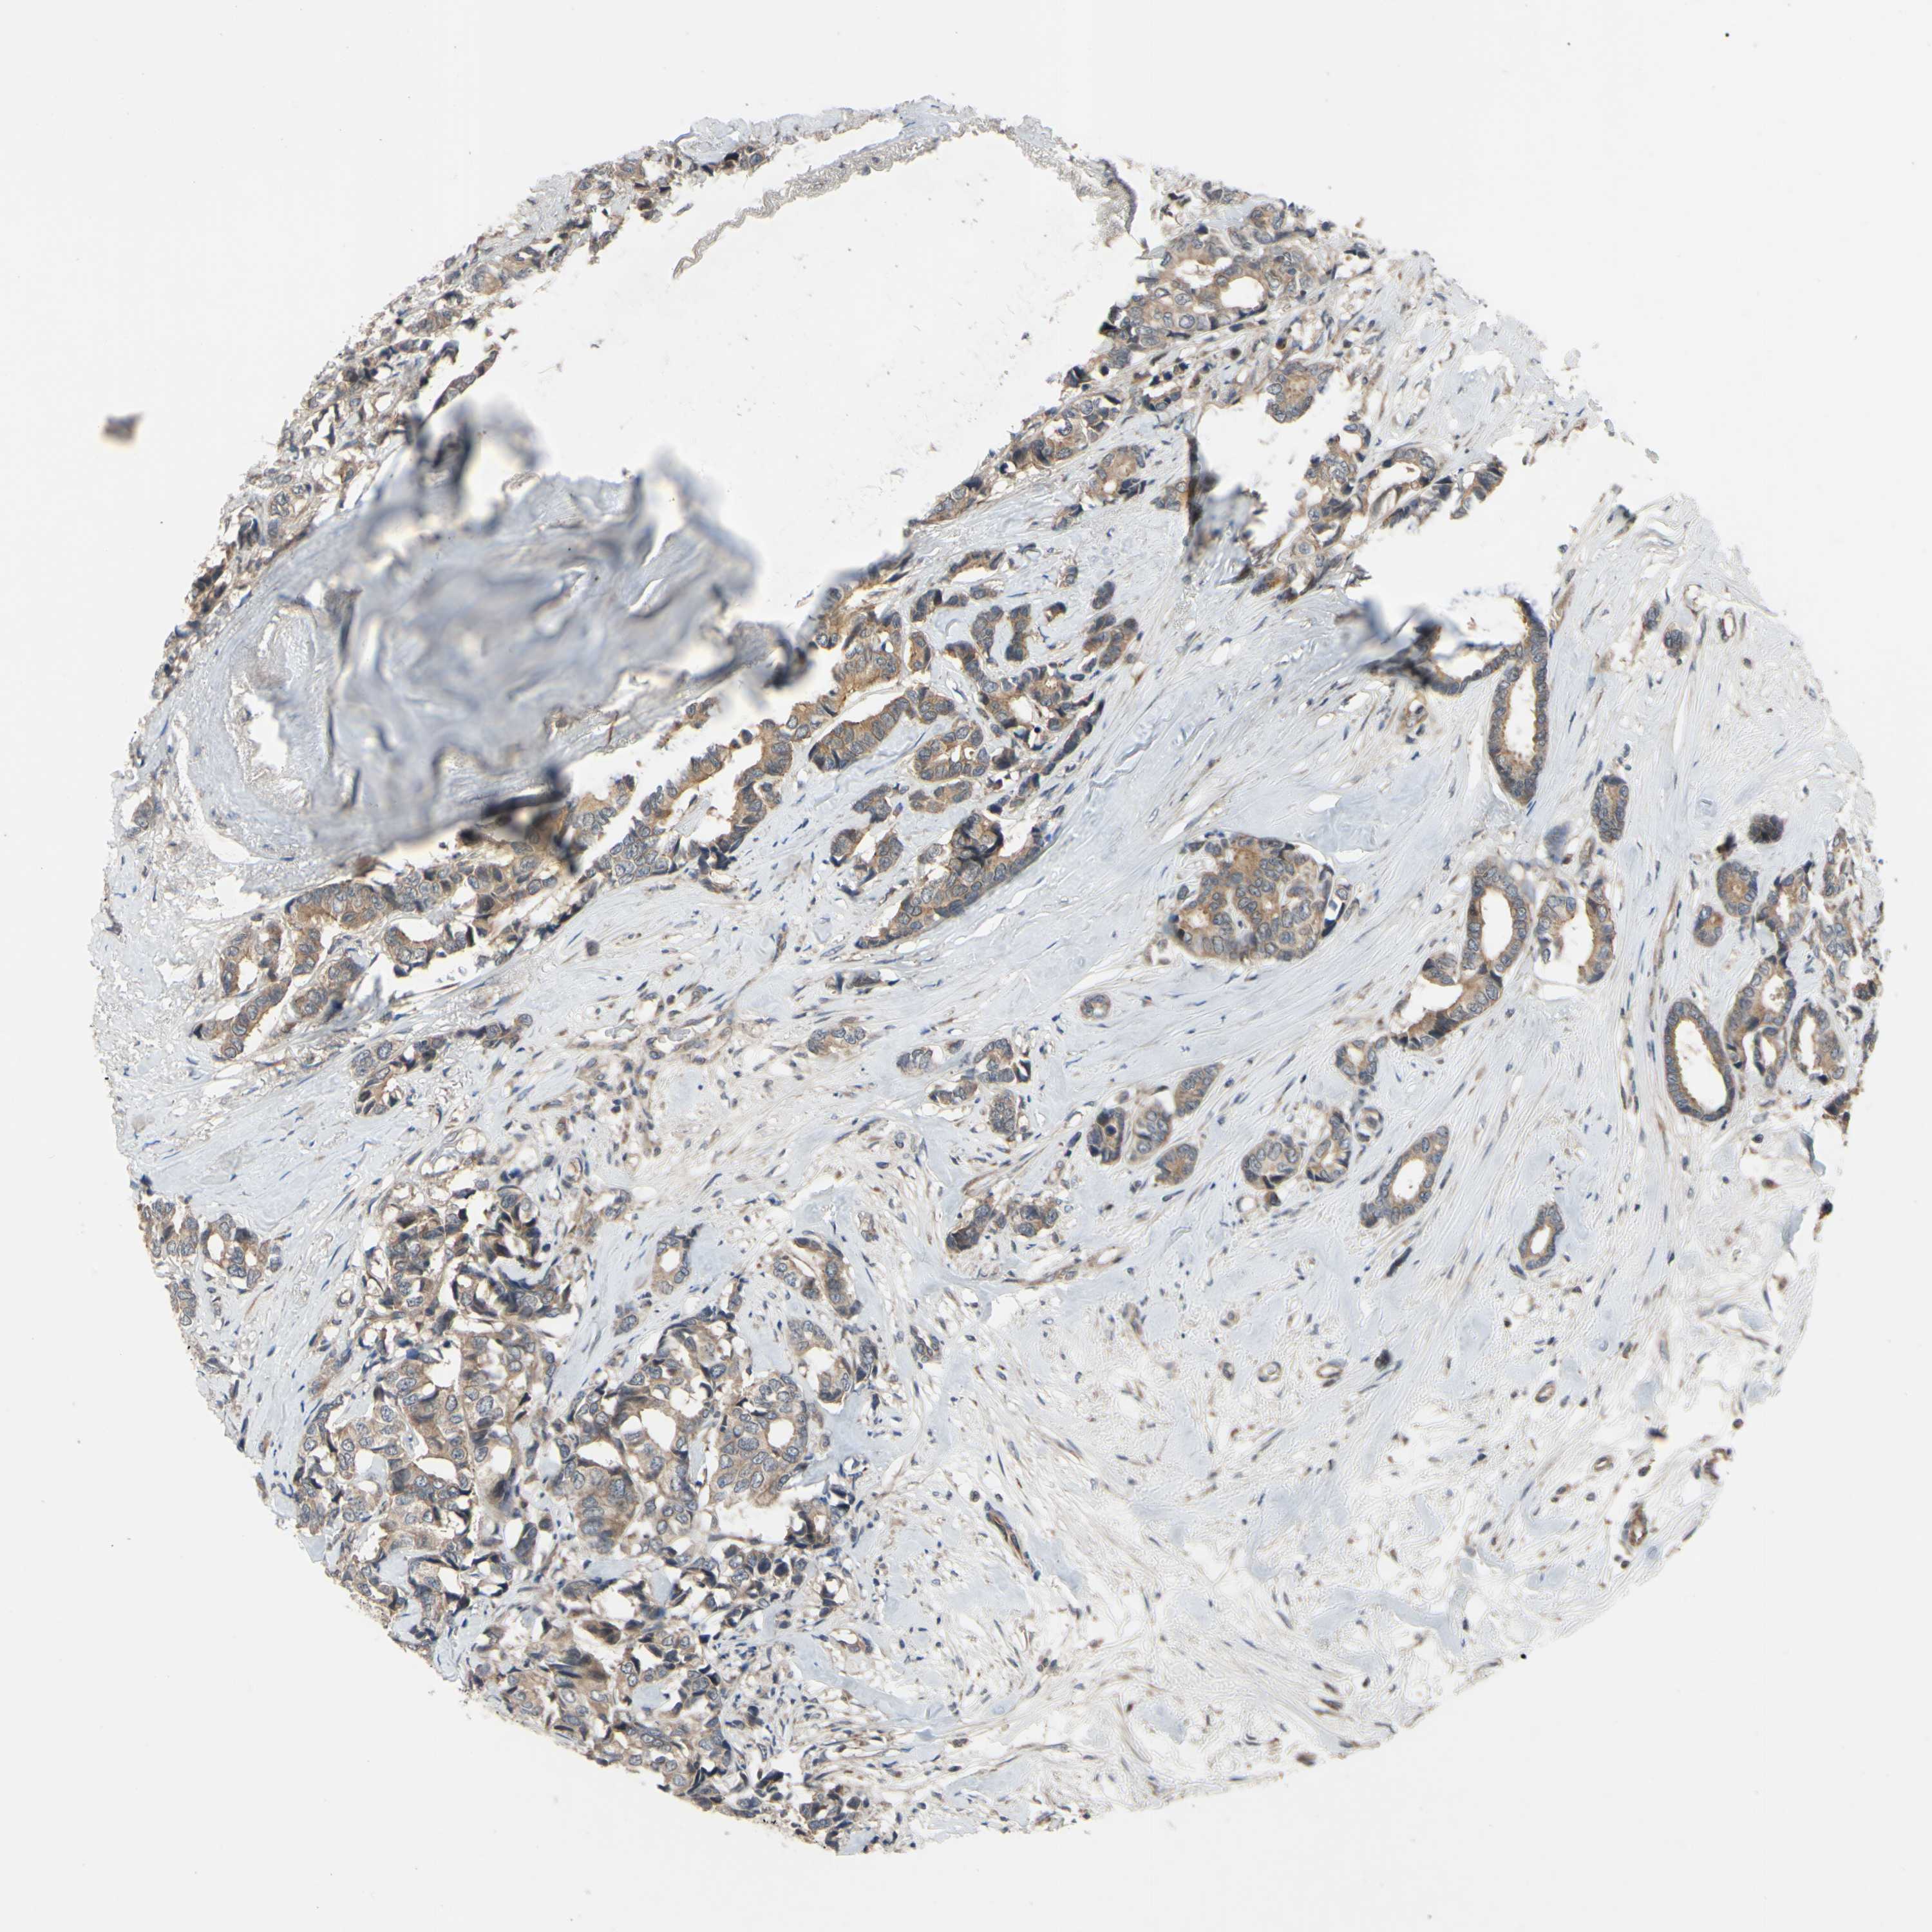

BRCA TCGA BRCA VALIDATION PROTEIN EXPRESSION

ANTIBODIES

AND

VALIDATION